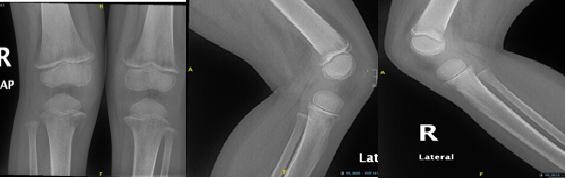

The radiographs bilateral ulnar symmetrical distal metaphyseal eccentric osteolytic lesions are seen with disruption of the medial cortex; however no periosteal reaction. Also, there is small osteolytic lesion within the distal radius (Figure 2). Both knees showed signs of osteopenia, the thick sclerotic metaphyseal line above a widened physis, and small beak-like excrescences at the metaphysis of both tibias (metaphyseal clefts). Ring of increased density surrounding epiphysis (Wimberger ring) (Figure 3). US guided aspiration of both knees show no signs of infection. MRI of wrist was done which show diffuse bilateral bone marrow oedema of the distal ulna and radius both sides. This is associated with evidence of diffuse periosteitis and soft tissue oedema however no apparent fluid collections. Subcutaneous oedema is also identified. No apparent acute fractures. No focal osseous lesions. Intact extensor and the flexor tendons bilaterally and bone: Generalized bone marrow oedema is seen more pronounced around the knee and wrist joints. (Figure 4).

Figure 3 Bilateral knee x ray AP and lateral view show joint effusion with osteopenia, the thick sclerotic metaphyseal line above a widened physis, and small beak-like excrescences at the metaphysis of both tibias (metaphyseal clefts).